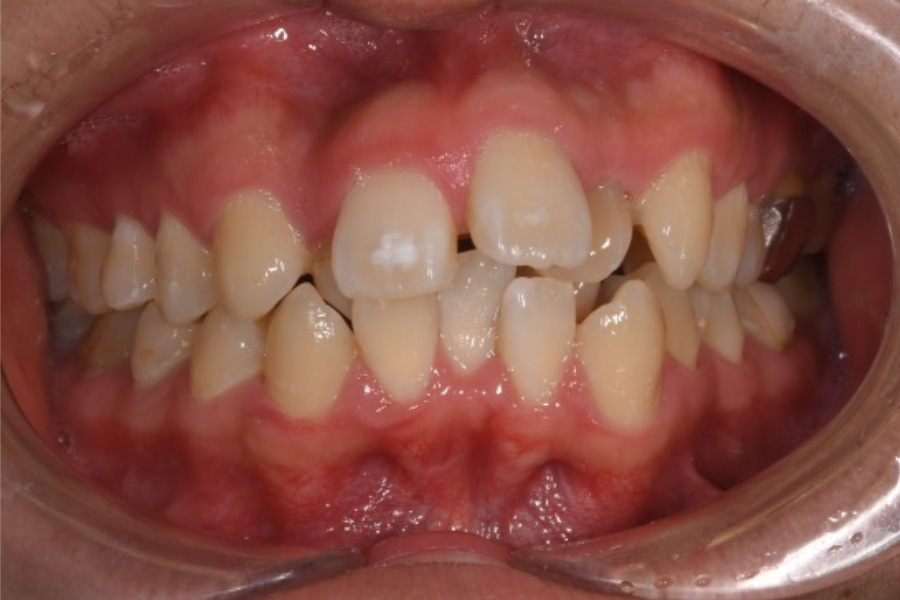

八重歯を含めた全体的なガタつき

【マウスピース矯正】

- 担当医

- -

- 主訴

- 八重歯を含めた全体的なガタつき

- 期間

- 2年

- 費用

- マウスピース矯正

1,024,000円(税込)

- 治療内容

- 目立ちにくいマウスピース矯正(非抜歯矯正)

歯と歯の間に隙間をつくることにより、歯列弓を広げながら治療を行いました。

- 治療に伴うリスク

- ・後戻りする可能性があるのでリテーナーを最低でも矯正期間以上はつけること

・稀にほっぺた、唇、舌などに口内炎や傷ができることがあります